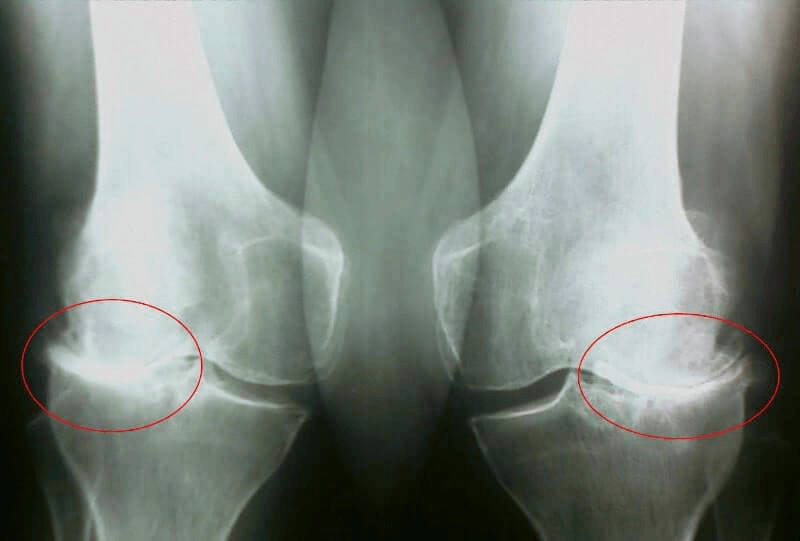

Rendgen sa očiglednim znacima artroze

- Dan 35: Otišao sam doktoru i napravio rendgenski snimak. Nema tragova artroze! Hrskavica u zglobovima kao kod 20-godišnjeg klinca.

Doktorka je rekla da je prethodni rendgen najvjerovatnije imao defekt, pa je dijagnoza artroze pogrešna.